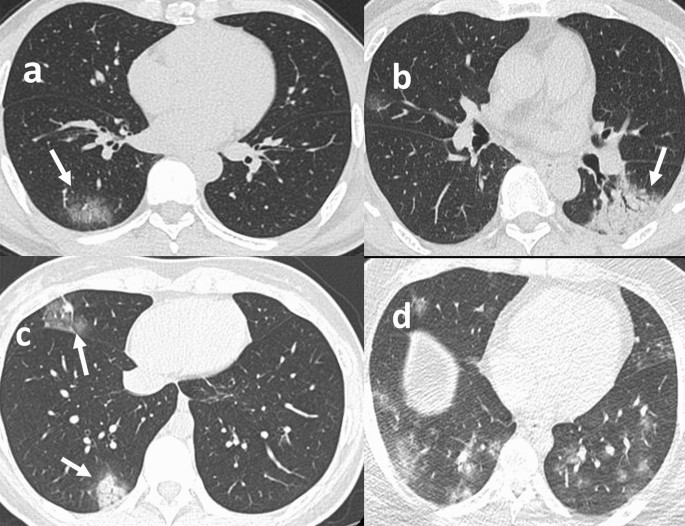

In the moderate group, 28 patients (87.5%) exhibited GGO, 14 (43.8%) exhibited consolidation, 17 (53.1%) exhibited local lesions and 22 (68.8%) exhibited unilateral lesions. FigureĀ 2 shows some typical examples of the CT images. The median CT score of the moderate group was 21,2,3. In contrast, the mild group did not exhibit characteristic changes according to the CT images.

Chest CT findings of COVID-19 pneumonia. (a) GGO; (b) consolidation; (c) multifocal lesions; (d) bilateral lesions.

In this study, 87.5% of the moderate cases exhibited GGO according to CT imaging, most of whom presented with a unilateral single focus. This finding was consistent with that reported in the literature39,40. However, Shi et al.41 and Bernheim et al.42 reported that most COVID-19 patients from Wuhan, China, exhibited multiple bilateral lesions. This inconsistency might be due to the younger age and non-severe disease of the patients involved in this study. In terms of dynamic imaging outcomes, COVID-19 patients present with a peak of variations approximately 10 d after disease onset, which suggests that the CT findings of COVID-19 are dynamic; therefore, timely rechecks are helpful for accurate and objective understanding of the progression of the disease43.